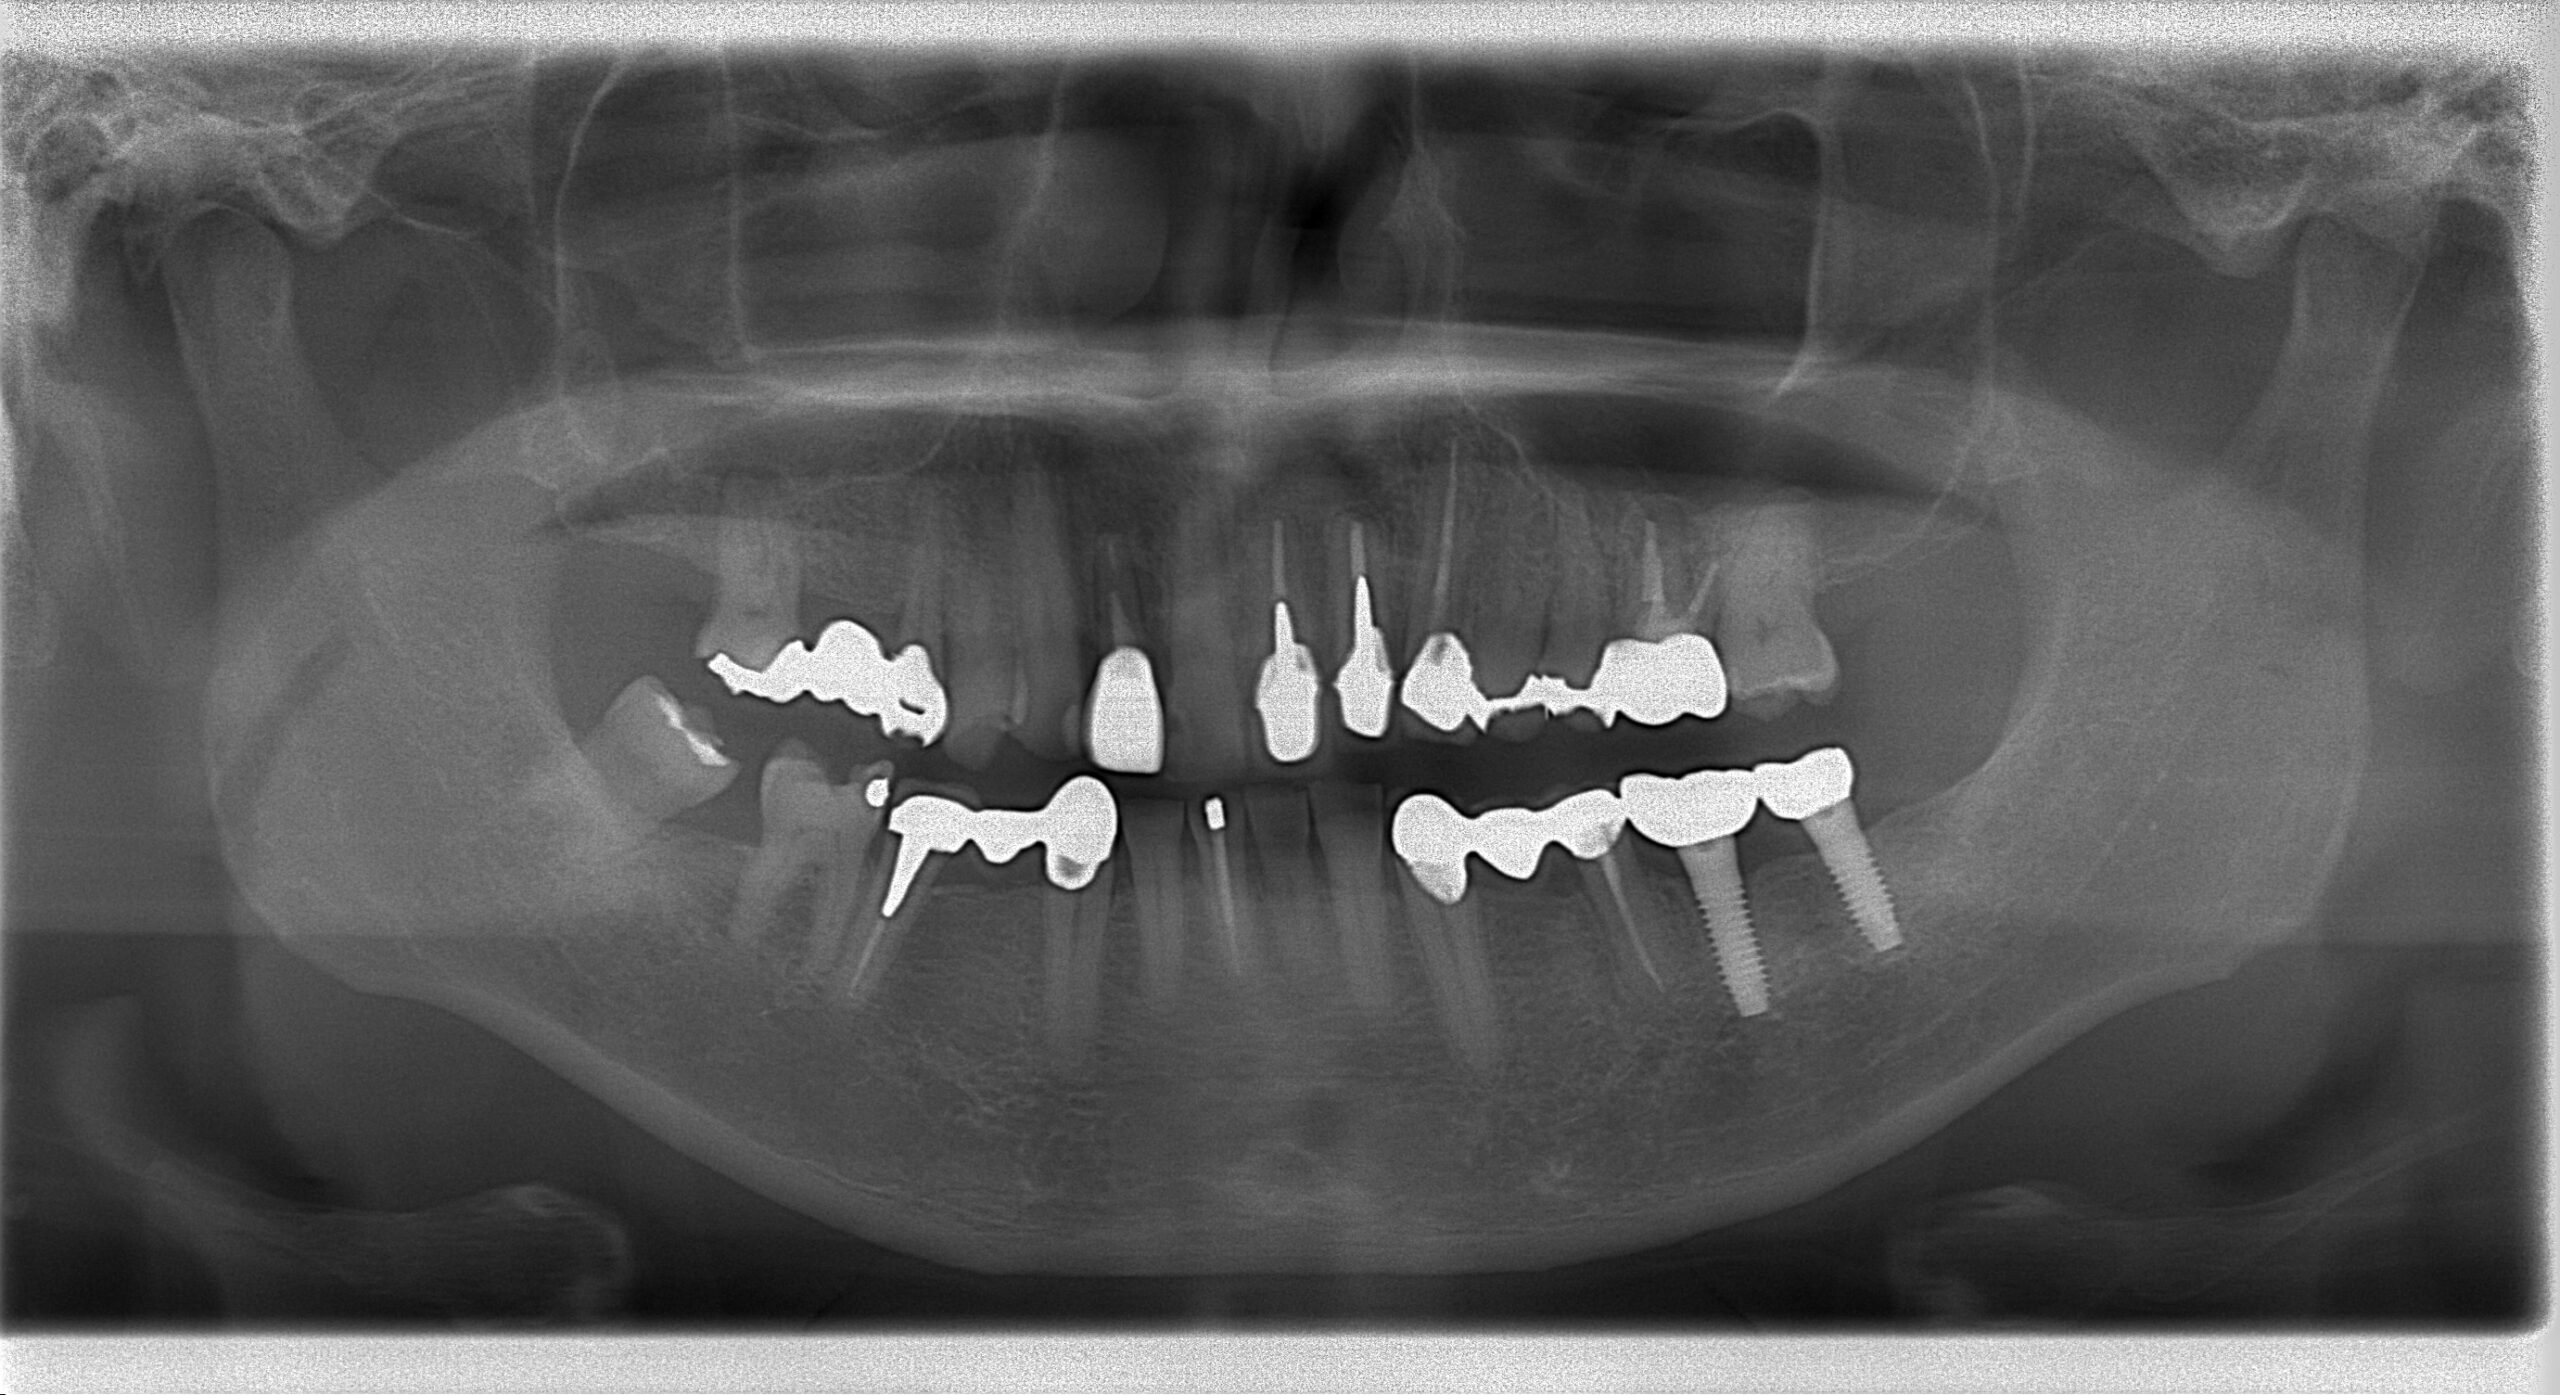

破折前のパノラマX線写真

昔使用していたミューワン1ピースインプラント体が患者様の咬合力により破折した症例です、初めての経験で滅多に起こりませんが起こると言うことですね…

通常破折したインプラント体を除去して再埋入するかと思いますが、骨結合している

インプラント体を除去するのは既存骨を削除し副作用が大きく、患者様の負担が増すため

今回は間のスペースに埋入しました。